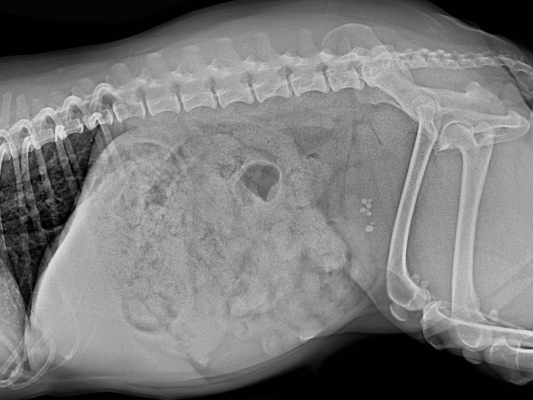

- 진단: 신체검사, 소변검사, 영상검사(방사선, 초음파 등)로 결석을 진단할 수 있습니다.